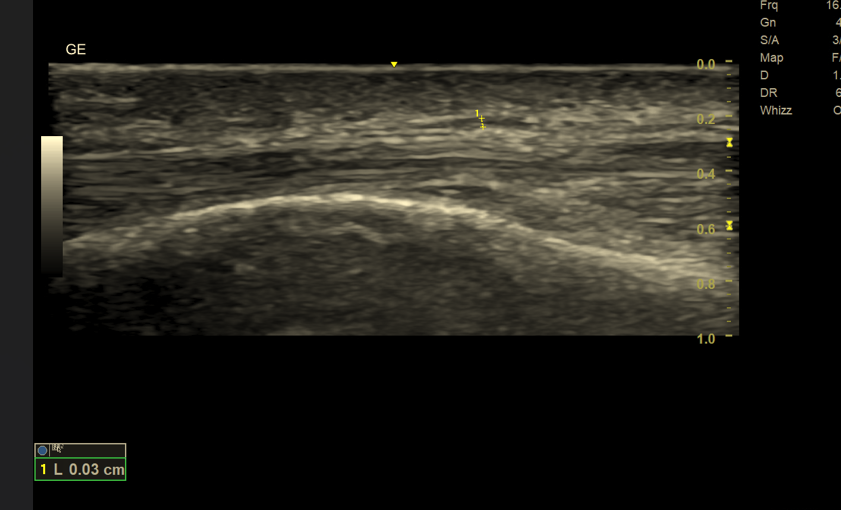

👉 Nerwy cienkie (< 3 mm) – diagnostyka praktycznie wyłącznie za pomocą USG wysokiej rozdzielczości

Nerwy cienkie (< 3 mm) – tylko USG wysokiej rozdzielczości

Dlaczego MR nie sprawdza się w ocenie cienkich nerwów?

Rezonans magnetyczny, mimo doskonałego kontrastu tkanek miękkich, nie oferuje wystarczającej rozdzielczości przestrzennej, aby wiarygodnie zobrazować bardzo cienkie struktury nerwowe.

➡️ USG zapewnia:

- rozdzielczość sięgającą 0,1–0,2 mm

- możliwość oceny fascikularnej budowy nerwu

- obrazowanie dynamiczne (ruch, ucisk, prowokacja objawów)

1. Rozdzielczość przestrzenna

- USG: zdecydowanie lepsza w ocenie nerwów cienkich i powierzchownych

- MR: ograniczona dla struktur < 3 mm

🔍 Wniosek: cienkie nerwy → tylko USG

Dlaczego USG jest lepsze od MR w ocenie cienkich nerwów?

USG oferuje znacznie wyższą rozdzielczość przestrzenną niż MR. Dzięki temu możliwa jest:

- ocena struktury pęczkowej nerwu,

- wykrycie pogrubienia, obrzęku lub ucisku,

- dokładna lokalizacja miejsca uszkodzenia.